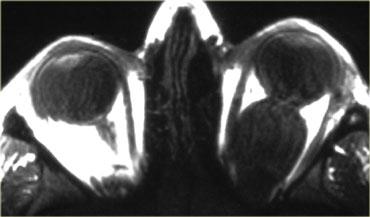

Hình bên trái là một nguyên nhân khác gây bạch đồng tử.

Đây là tồn lưu dịch kính nguyên phát tăng sản (PHPV).

Có sự tồn tại của ống hyaloid khi động mạch hyaloid không thoái triển.

Trên hình ảnh, chúng ta thấy một ống tồn lưu đi từ thần kinh thị giác đến thủy tinh thể.

Ngoài ra còn có bong võng mạc (gặp trong 30-55% trường hợp) và lưu ý tình trạng nhãn cầu nhỏ (microphtalmia).

PHPV là nguyên nhân thường gặp thứ hai gây bạch đồng tử.

Những bệnh nhân này cũng có thể phát triển glaucoma và đục thủy tinh thể.